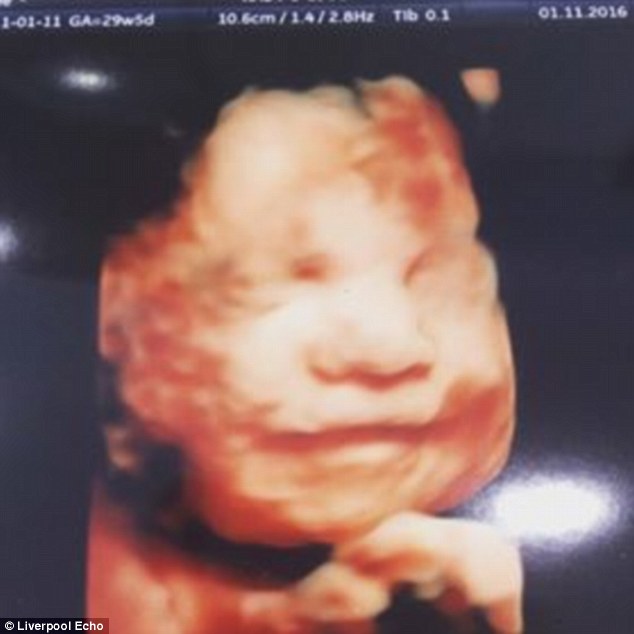

LIVERPOOL – Il figlio che ha in grembo sorride e la mamma, dopo aver visto la scansione 4D, è rimasta a dir poco sconvolta. Aimee Fagan vive a Kirkby nel Merseyside inglese. Come racconta il Daily Mail, la 27enne madre di due figli non poteva credere all’immagine che le ha consegnato l’ecografista. Sua figlia che nascerà il prossimo gennaio e nell’immagine postata anche in questo articolo, ride divertita.

Aimee ha due figli: Mollie di tre anni e Macy di sei: “L’ecografista mi ha detto di non aver mai visto un bambino ancora in pancia sorridere così tanto. Prima di riuscire a vedere la scansione , la mia bambina era nascosta e non riuscivamo a vederla. Alla fine, mia figlia Mollie ha cominciato a parlare e lei, la mia terza figlia, deve aver sorriso sentendo la voce della sorella”.

Vedere una cosa del genere, effettivamente è piuttosto raro. I figli, secondo gli esperti imparano a sorridere dopo la nascita copiando le espressioni facciali dei loro genitori. In questo caso però, il sorriso potrebbe anche essere un effetto ottico dovuto all’ecografia. L’unica certezza è che molto probabilmente, la terza figlia di Aimee sarà una bambina serena.